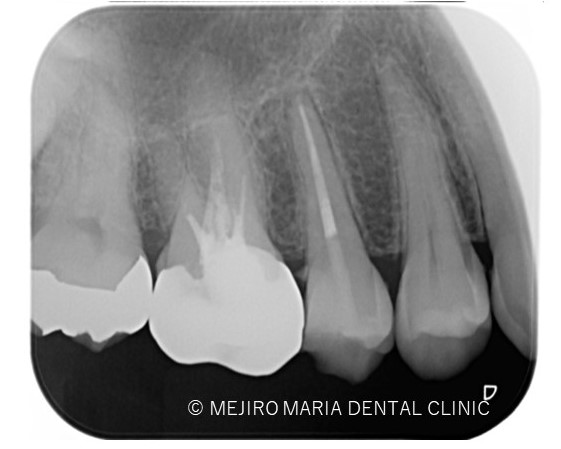

治療後の様子

3ヶ月後に経過観察を行い。最終的な根管治療の予後を確認する予定です。 可及的速やかに暫間冠の作製、問題なければ最終補綴処置に移行します。

今回は右上5番に対しての根管治療における、根尖3mmで分岐する根管へのアプローチでした。

当院のホームページでも記載があるように、根尖3mmは非常に複雑な形態をしていることから、根管治療でのアプローチの限界があるのも事実です。